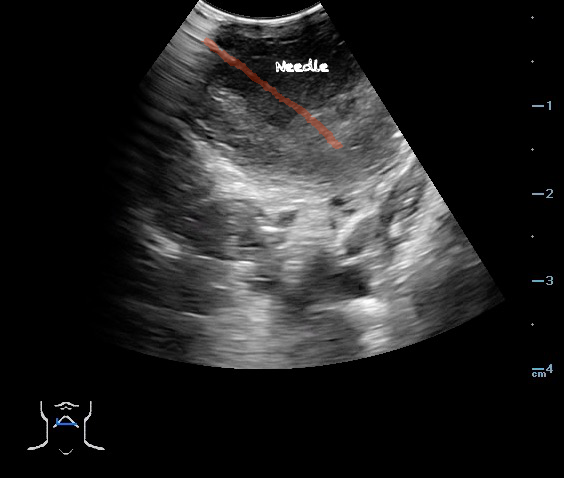

- Ultrasound-guided needle aspiration of a PTA:

- The depth of the abscess cavity from the mucosal surface should be noted to determine the length of the needle required to drain the abscess.

- Figure 45. and 46. PTA aspiration

- The carotid artery is seen as an anechoic tubular structure along the posterolateral aspect of the tonsil on ultrasound. Its relationship to the abscess cavity should be determined. Color Doppler can help locate the carotid artery.